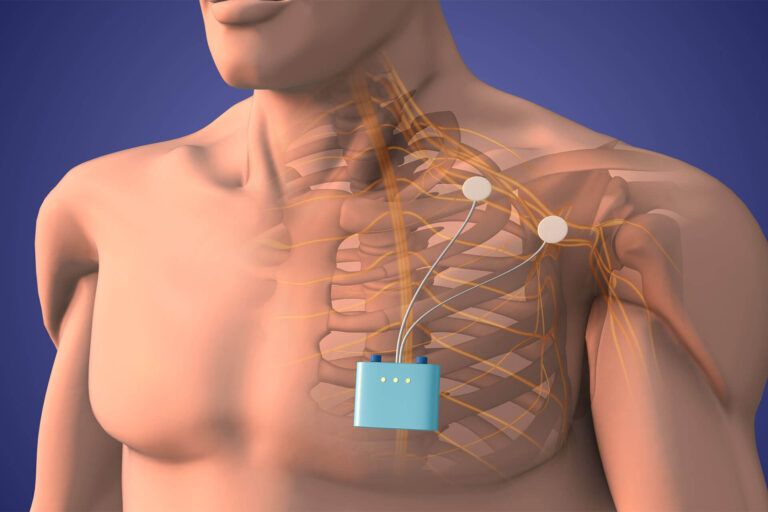

At Midwest Headache and Spine Pain Institute, we adopt a multidisciplinary approach to treat chronic pain. We provide a variety of pain interventions, which are done both fluoroscopically and ultrasound guided.

Please read below to learn about the services we provide.